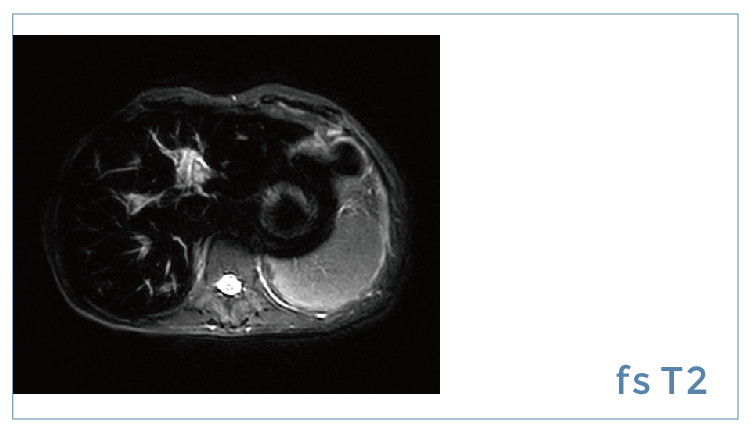

【朗润影像档案】20190914磁共振影像病例结果讨论

【朗润影像档案】磁共振影像病例分享(编号20190914)